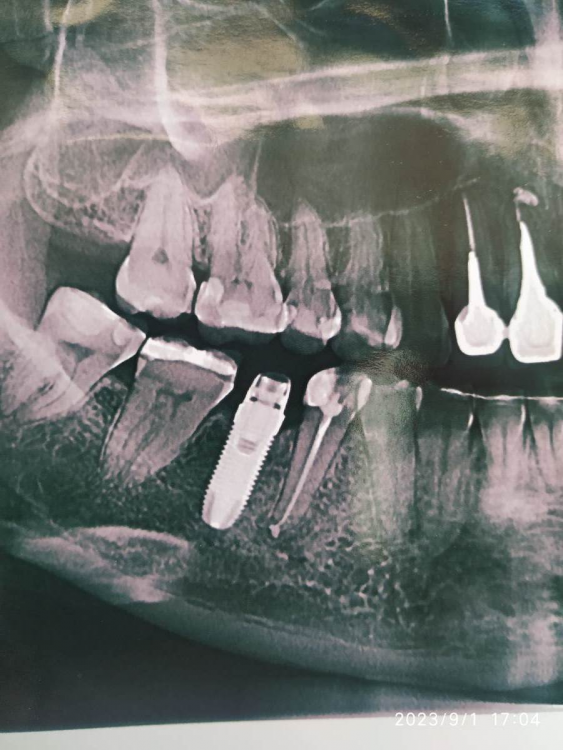

gum Опубликовано 18 сентября, 2023 Поделиться Опубликовано 18 сентября, 2023 Здравствуйте, коллеги подскажите пожалуйста, что за имплантат? Ссылка на комментарий

АнтонТЛТ Опубликовано 19 сентября, 2023 Поделиться Опубликовано 19 сентября, 2023 Какой-то бранемарк Ссылка на комментарий